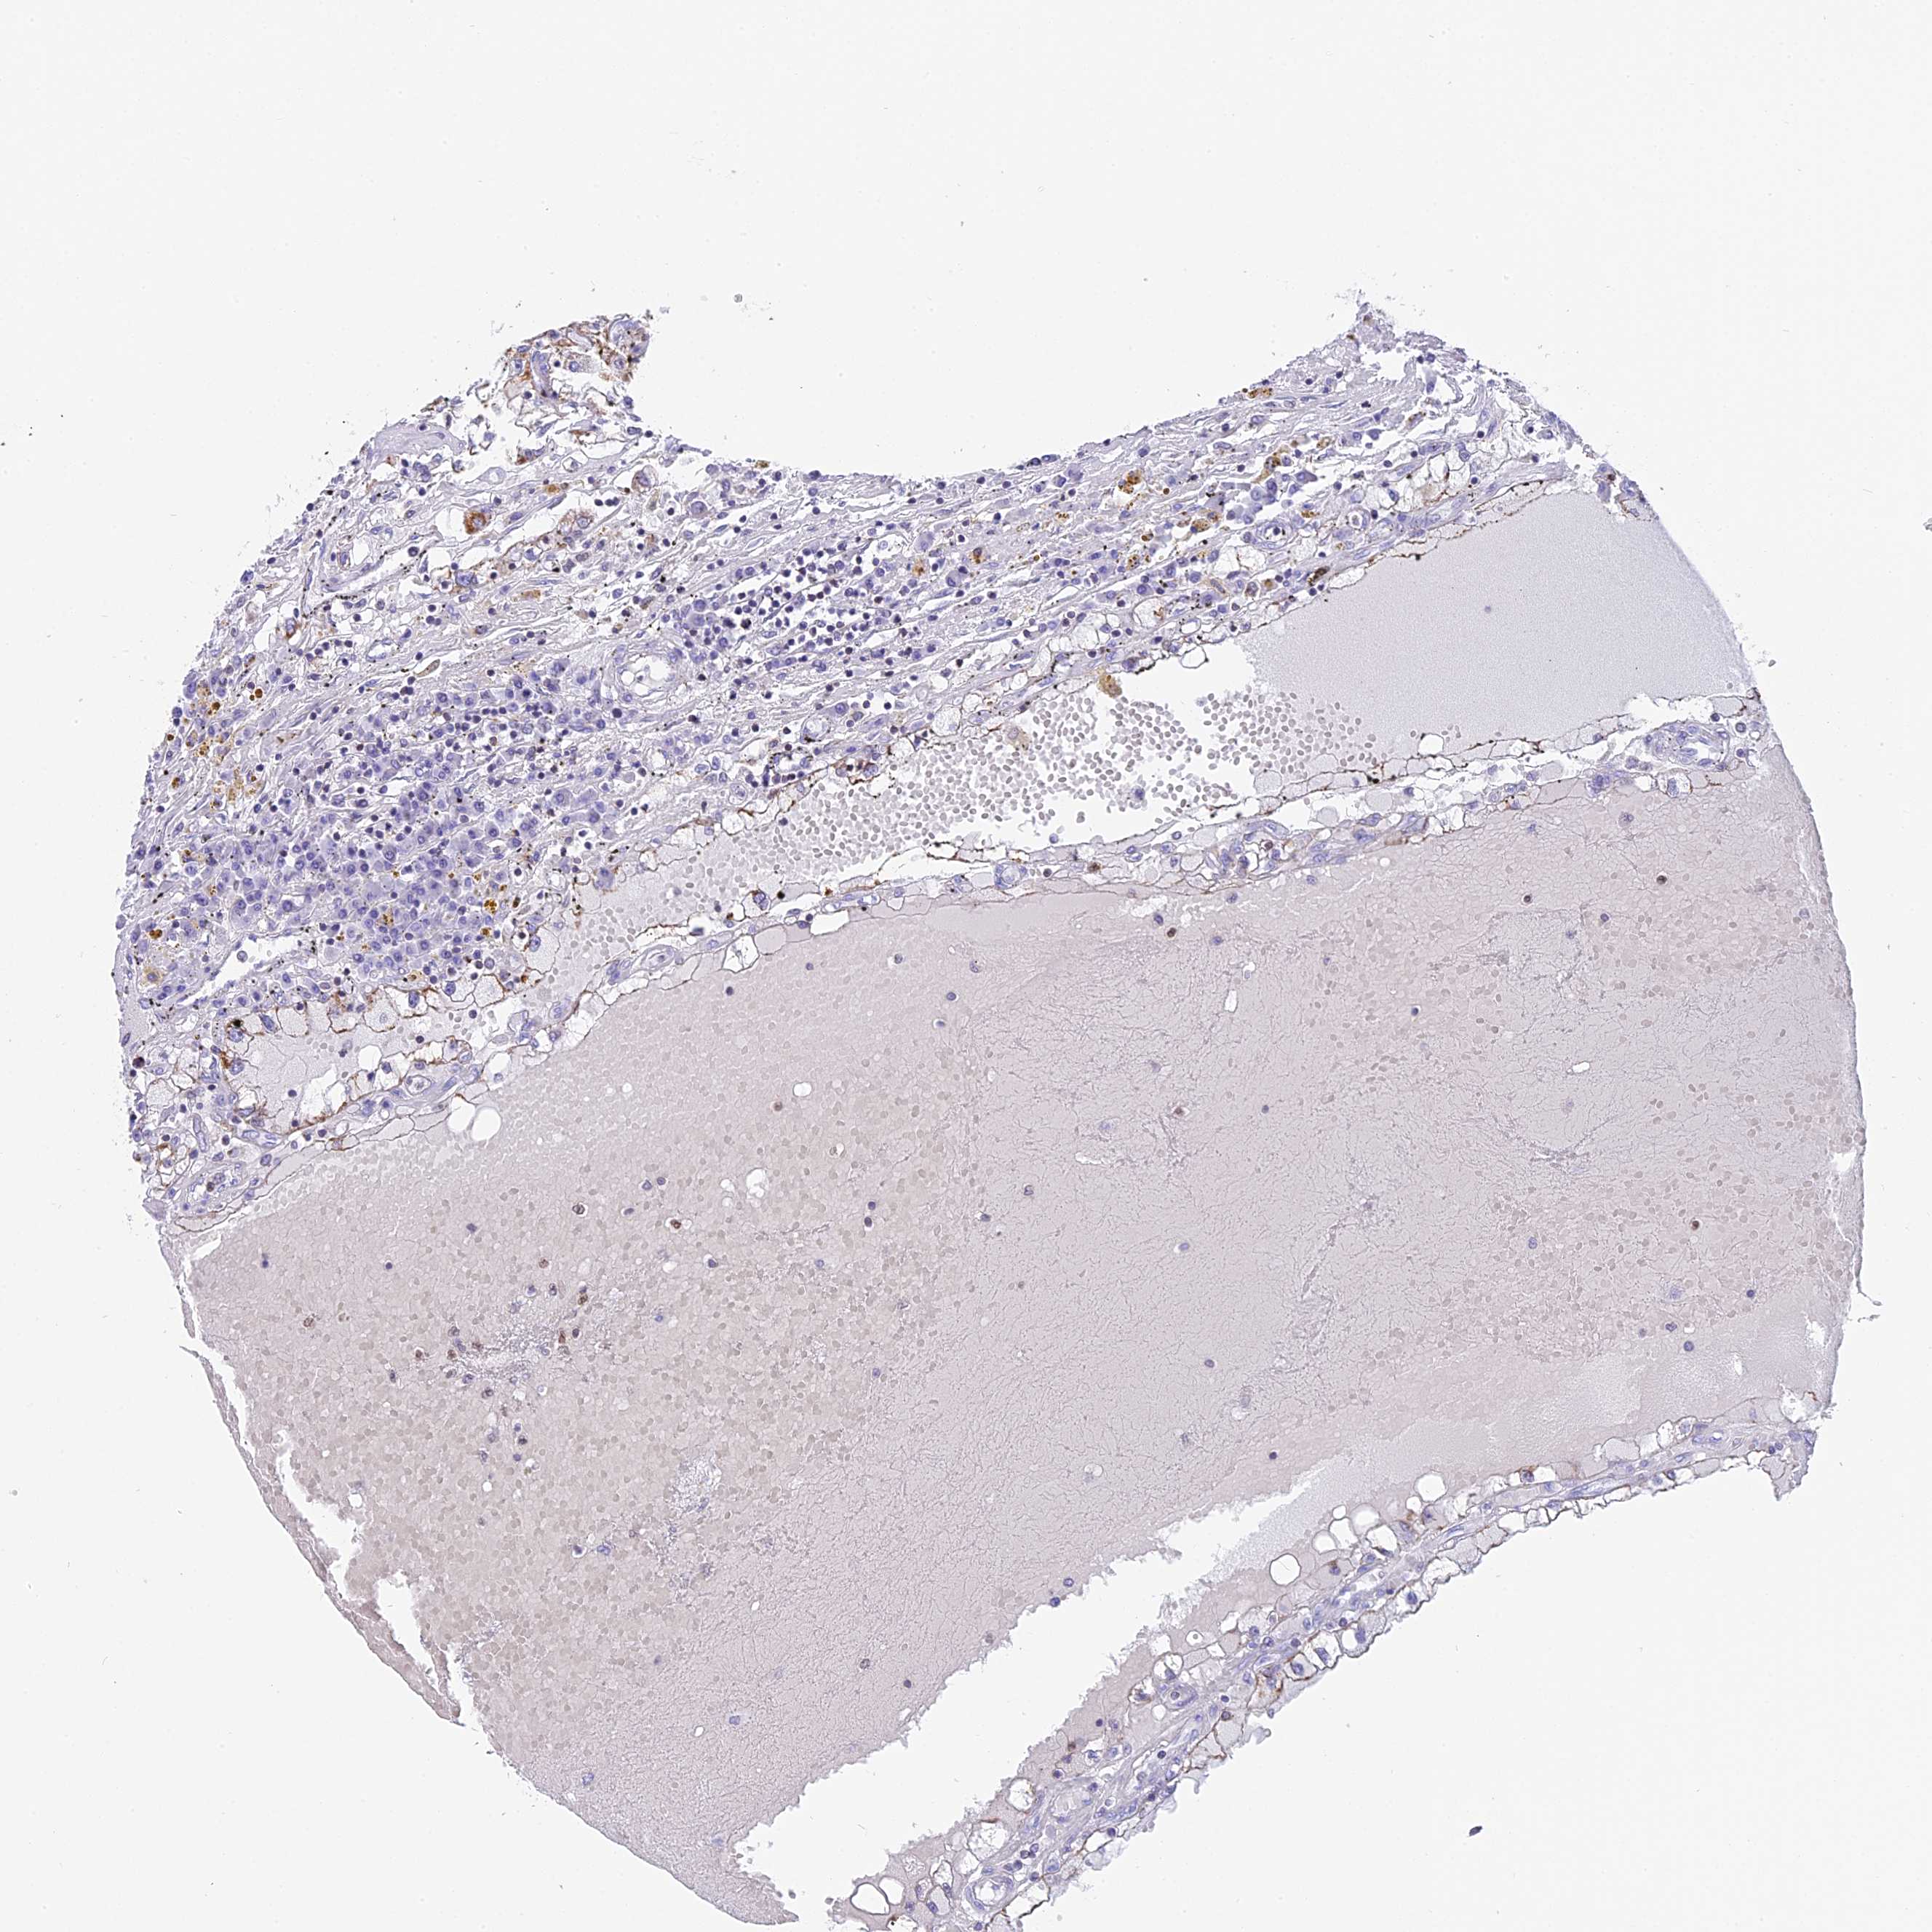

CANCER RENAL CANCER Show tissue menu

KICH TCGA KIRC TCGA KIRC VALIDATION KIRP TCGA PROTEIN RCC CPTAC PROTEIN EXPRESSION

ANTIBODIES

AND

VALIDATION